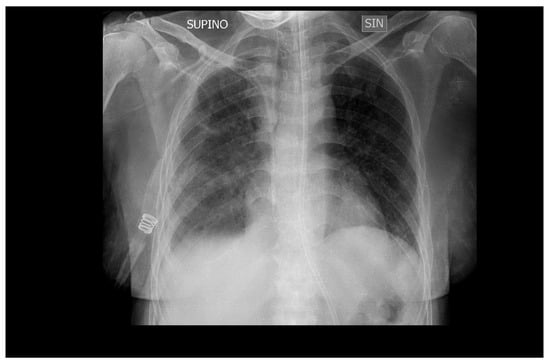

Mechanical ventilation was stopped after 10 days (Figure 4), and the patient was transferred to the medical department where she continued therapy with ganciclovir for another two weeks before being discharged to her home.

Figure 4.

Chest X-ray of the patient extubated after 10 days of ganciclovir therapy shows almost complete resolution of bilateral interstitial pneumonia. SUPINO: supine; SIN: left.